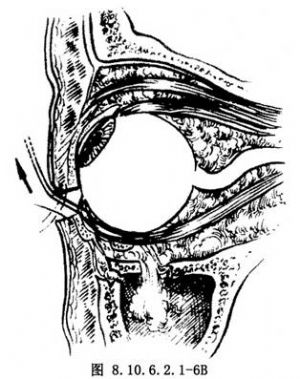

10.3 3.拔出被嵌顿的组织

将眶下壁骨折充分暴露,直到缺损的后部边界,用牵拉器将下直肌、下斜肌及眶内软组织推向上方,用骨膜分离器及组织钳伸入骨质缺损处,夹住被嵌顿的组织,从骨折部位向上提拔,将被嵌顿组织提起后,再次重复牵拉试验,直至眼球各方向运动均恢复正常(图8.10.6.2.1-6A、B)。然后取咬骨钳取出碎骨,取吸引器伸入上颌窦吸出血块及碎骨片。